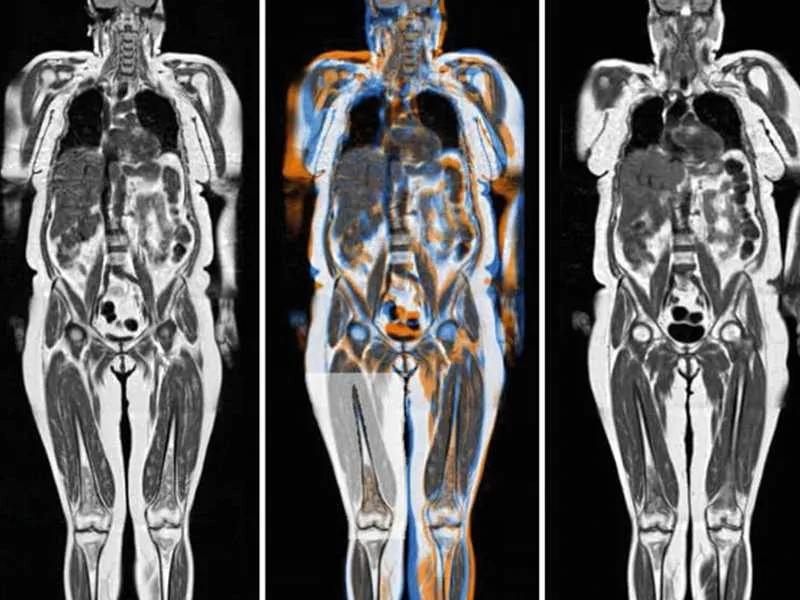

Tüm vücut MR, manyetik rezonans görüntüleme teknolojisi kullanılarak vücudun tamamının ayrıntılı bir şekilde taranmasıdır. Radyasyon içermeyen bu yöntem, manyetik alan ve radyo dalgaları yardımıyla organların ve dokuların yapısını detaylı bir şekilde gösterir. Doktorlar, bu görüntüleri kullanarak hastalıkları teşhis eder ve tedavi planlarını oluşturur.

Tüm vücut MR ile kanser türleri, tümörlerin yayılımı, inflamatuar hastalıklar, enfeksiyonlar, dejeneratif hastalıklar, sinir sistemi bozuklukları ve damar hastalıkları teşhis edilebilir. Bu yöntem, özellikle erken teşhis gerektiren hastalıklarda büyük önem taşır ve doktorların doğru tedavi yöntemini belirlemelerine yardımcı olur.

Tüm vücut MR ile vücudun iç yapısı detaylı bir şekilde görüntülenir. Kanserler, tümörler, enfeksiyonlar, inflamatuar hastalıklar, sinir sistemi bozuklukları ve damar problemleri gibi birçok hastalık tespit edilebilir. Bu yöntem, hastalıkların erken teşhisi ve tedavi planlaması açısından büyük önem taşır.